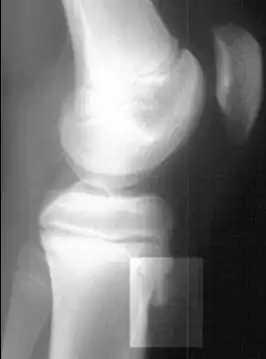

Radiografía lateral de la rodilla demostrando fragmentación del tubérculo tibial, con tejido sobreabundante | ||

Rayos X mostrando la enfermedad de Osgood-Schlatter -